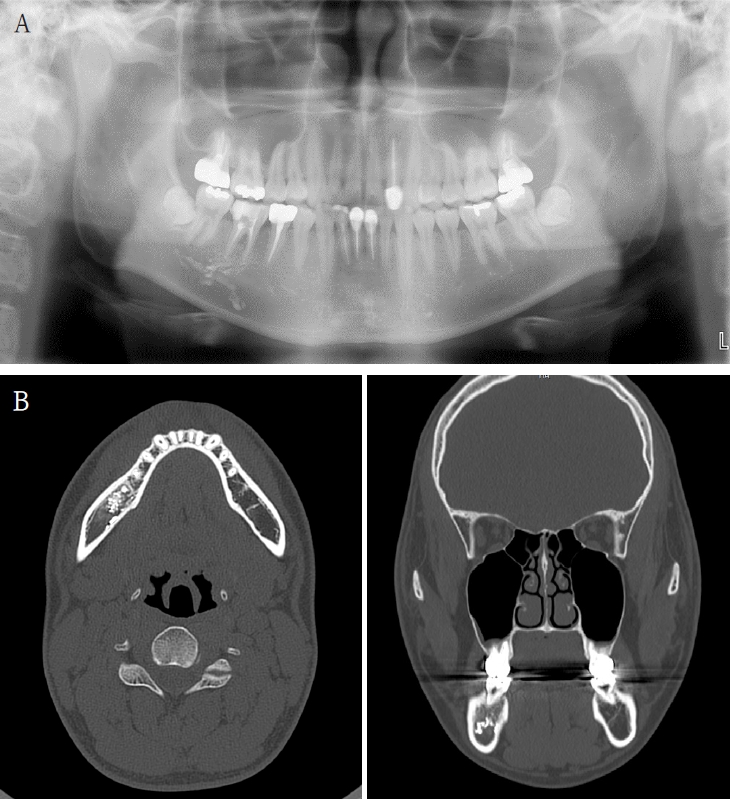

Case 3

Figure 3.

A. Pre-op panoramic radiograph of Case 2 patient. B. Pre-op CBCT of Case 2 patient.